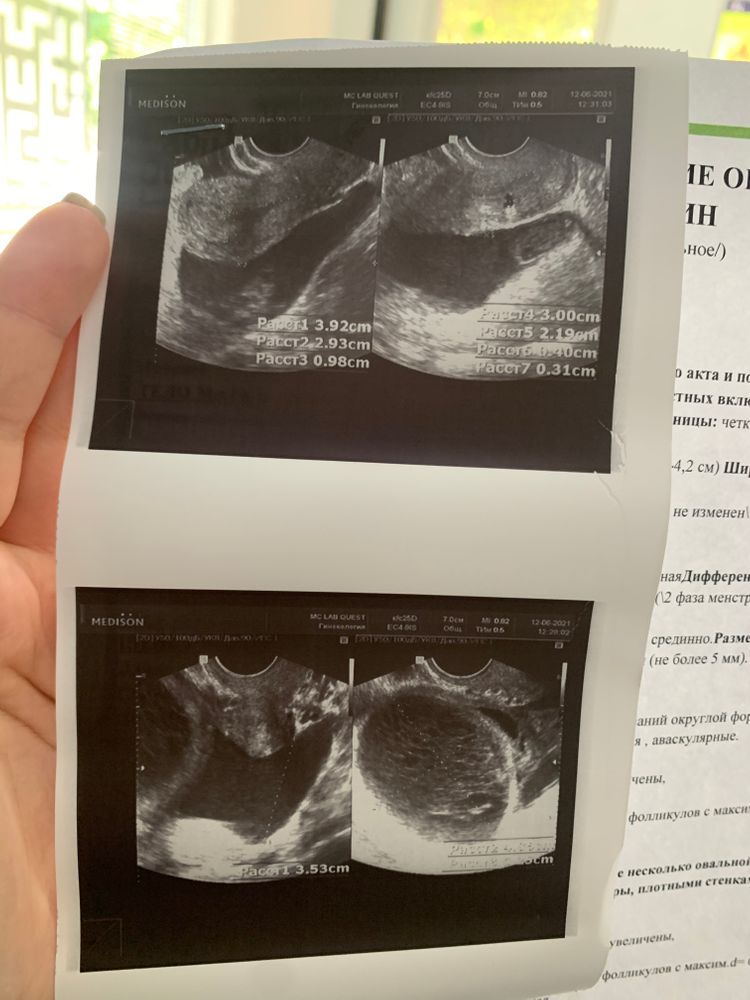

Не гинеколог, но кистознтр образование яичника, довольно большое, которые скорее всего возможно подлежит хирургическому удалению